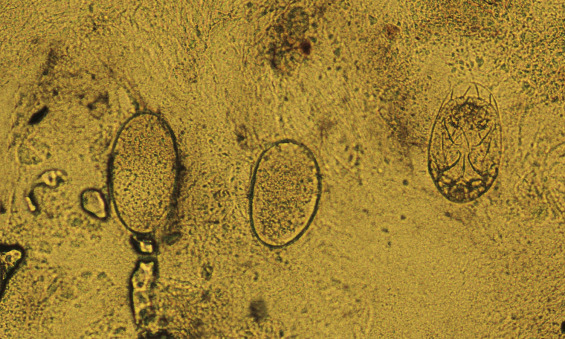

Infestation begins when a fertilized female mite arrives on the skin surface. Within an hour, the female excavates a burrow in the stratum corneum (dead, horny layer) ( Fig. 15.2B ). During the mite’s 30-day life cycle, the burrow extends from several millimeters to a few centimeters in length. The burrow does not enter the underlying epidermis except in the case of hyperkeratotic Norwegian scabies, a condition in which scaly, thick skin develops in intellectually disabled, immunosuppressed, or elderly patients in the presence of thousands of mites. Eggs laid at the rate of two or three a day ( Fig. 15.3 ) and fecal pellets (scybala) are deposited in the burrow behind the advancing female. Scybala are dark, oval masses that are seen easily with the eggs when burrow scrapings are examined under a microscope. Scybala may act as an irritant and may be responsible for some of the itching. The larvae hatch, leaving the egg casings in the burrow, and reach maturity in 14 to 17 days. The adult mites copulate and repeat the cycle. Therefore, 3 to 5 weeks after infestation, there are only a few mites present. This life cycle explains why patients experience few, if any, symptoms during the first month after contact with an infested individual. After a number of mites (usually less than 20) have reached maturity and have spread by migration or the patient’s scratching, the initial, minor, localized itch evolves into intense, generalized pruritus.

A definite diagnosis is made when any of the following products are obtained from burrows or vesicles and identified microscopically: mites, eggs, egg casings (hatched eggs), or feces (scybala). About 5 to 15 female mites live on a person infected with classic scabies. Failure to find a mite is common and does not rule out the diagnosis of scabies. Hundreds or thousands of mites can occur in cases of crusted scabies. Mites are easily demonstrated in such patients.